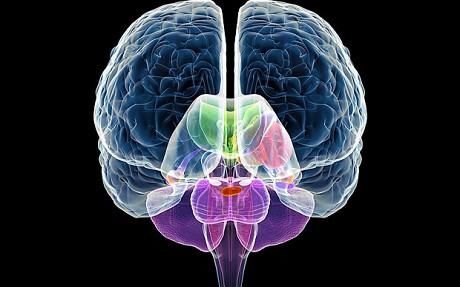

大脑采样

实验三:从活体中取出脑细胞

前提:尽管科学家意识到我们生活的环境能够改变DNA,他们却鲜有所谓表观遗传变化的发生和带来后果的记录实验例子。在动物身上进行的这项研究表明这种后果意义深远。利用大脑采样,我们能够了解虐待儿童神经系统产生的真正影响,还可能了解更多潜在的影响。

科学家进行活检时利用手术获取大脑细胞,一小片足够了。假设不会造成任何干扰,对大脑的伤害也是最小的。

代价: 这项实验能够解开大脑是如何学习的。通过进行与DNA有关的实验,我们能够更好地理解生活是如何改变修补我们从上辈遗传的基因。